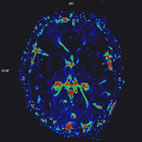

最新的SWI影像,能精確地顯示腦部微小的靜脈血管結構,圖中?色的病灶是一個出血的血管瘤。